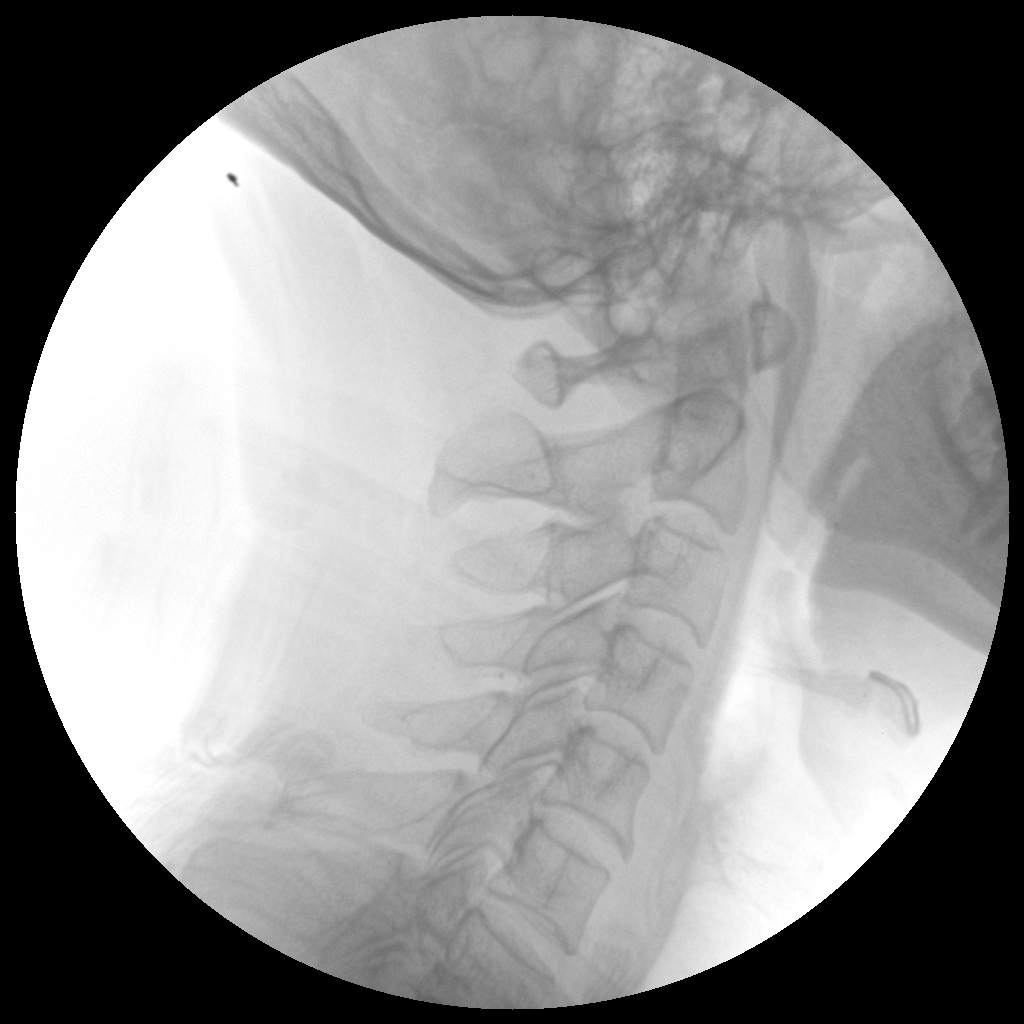

●經(jīng)典影像工作站,可隔室操作避免輻射

●全數(shù)字化百萬(wàn)像素影像系統(tǒng),圖像清晰

●靈活的C臂機(jī)架設(shè)計(jì),滿足臨床大范圍運(yùn)動(dòng)